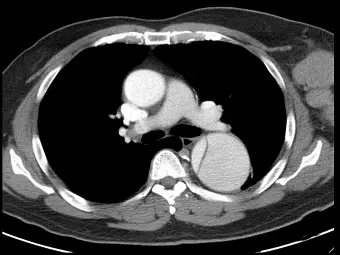

男性高血壓患者突然胸痛,注射對比劑後的電腦斷層影像如下圖,最有可能的診斷為何?

- 本圖為注射對比劑後的胸部電腦斷層掃描(Contrast-enhanced CT)軸切面(Axial view)影像,切面位置約在主肺動脈(Main pulmonary artery)分岔處的層級。

- 影像中可見**升主動脈(Ascending aorta)**顯影均勻,未見明顯異常構造。

- 位於脊椎前方偏左的降主動脈(Descending aorta)明顯擴張,且管腔內可見一條清晰的弧線狀透亮構造,此為典型的內膜瓣(Intimal flap)。

- 內膜瓣將降主動脈的對比劑血流管腔分隔為兩個部分,形成典型的**雙管腔(Double lumen)**標誌,即真腔(True lumen)與假腔(False lumen)。這是主動脈剝離在電腦斷層影像上最具特異性的診斷依據。

- (A) 主動脈剝離(Aortic dissection):正確。患者為高血壓男性且有突發性胸痛,為典型的主動脈剝離高危險群與臨床表現。對比劑增